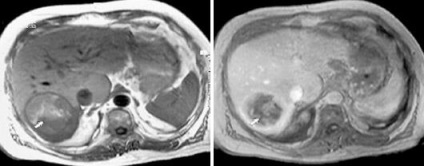

Natív és postkontrastnye MR hemangioma diffúz típusú amplifikációs.

MRI az UCP natív és dinamikus kontrasztos tanulmány. MRI dinamikus kontrasztanyagos megbízhatóan érzékeli, és lehetővé teszi egyedi képződése jellemzi a máj, mint a csomóponti noduláris hiperplázia.

Noduláris hiperplázia Máj